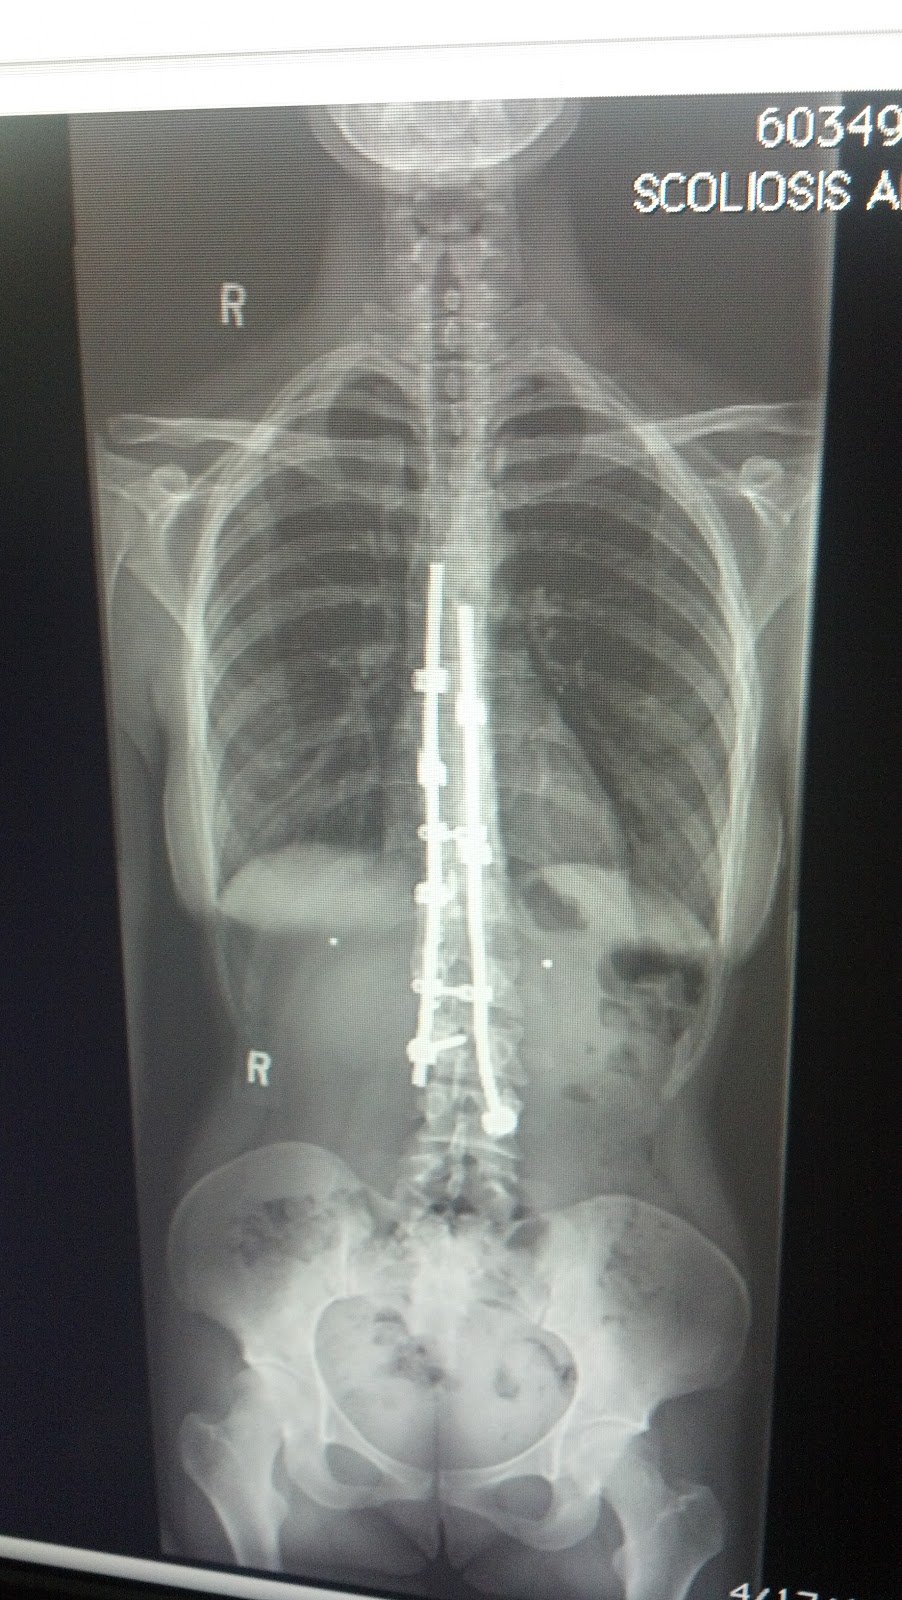

#1 — 29,000 adolescent surgeries each year every year in the united states alone, approximately 29,000 scoliosis surgeries are performed on adolescent patients. The goal of these nonfusion surgeries is to correct the scoliosis but still allow for the spinal growth and motion. Although the largest increases were for spondylolisthesis (+47,390 operations, 111%) and scoliosis (+16,129 operations, 186.6%), disc degeneration, herniation, and stenosis combined to accounted for 42.3% of total elective lumbar fusions in 2015.

- had the most current experience (how many rod surgeries per year over how many years), * had operated on fa�ers. Magnetically controlled growing rods help children with early onset scoliosis avoid multiple surgeries. Idiopathic scoliosis ‘idiopathic’ means there is no known single cause.